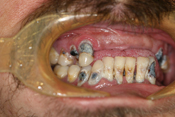

WORST TEETH Pictures from Warren Dentistry

This can happen to your teeth when proper Dental Hygiene is not practiced.

Patient 1